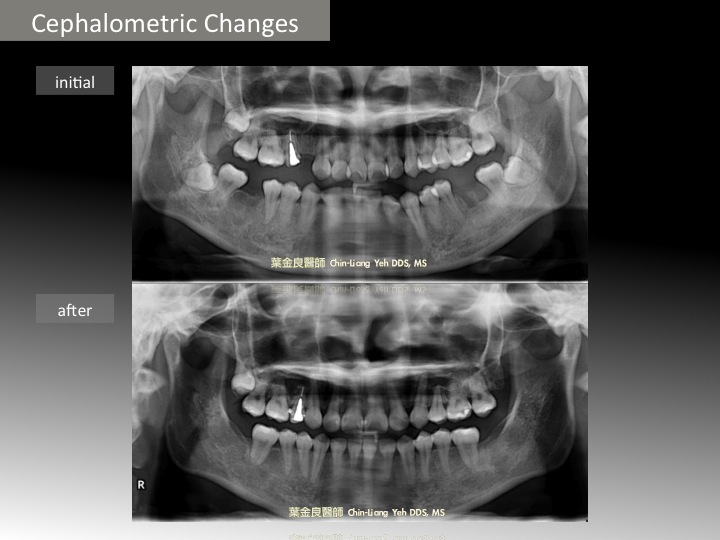

近來有許多矯正求診的患者因為下顎第一大臼齒太早喪失,已經導致第二大臼齒傾斜,而考慮到矯正治療。大多數這樣的病患,都曾被告知可能需要人工植牙或牙橋的膺復假牙治療。

下顎第一大臼齒太早喪失,常常有上顎對咬牙因為咬不到下方牙齒而產生過度萌發。亦或已經產生鄰牙的歪斜,這些都會造成假牙製作和人工植牙上的困難。

所以,合併臉型與大臼齒傾倒的問題是『複雜且困難』的矯正治療,但對病患本身而言的『危機』卻可能是『轉機』!因為缺牙問題,造成空間也許可以被矯正醫師拿來應用,而避免拔牙創造空間的治療方式。

如果是有上下牙齒外突的病患,原本需要拔除上下顎第一小臼齒的,此時只要確定大臼齒的缺牙區扶正,且可以用來將前牙後移關閉,那剩下只需要拔除上顎的第一小臼齒,加上前牙的後移即可以有完美的矯正治療!

反觀其中的治療缺點包含:第一,『錨定作用的不夠』(因為後牙喪失),可能需要額外的錨定作用(如骨釘)來協助前牙後移,否則會因位『前牙後移的位置不夠』,造成臉型美觀問題無法徹底改善,

第二,另一項缺點是『治療時間的加長與困難度增加』。因為需要將大臼齒扶正外,還要將前牙移動到較遠的距離(一般而言,是關閉第一小臼齒,如今是關閉第一大臼齒)。

第三,缺牙空間可能無法『完全』關閉。原因是因為缺牙過久,齒槽骨已經過度萎縮。此時可能需要加作齒槽骨手術,來增加寬度。

Anyhow, 如果這樣的治療計畫是可行的,那對病患而言,不僅可省下昂貴的植牙的費用或因做牙橋而磨去自然牙的不可逆治療外,顏面與咬合的美觀將會是最完美的結果 。否則,考慮其美觀與咬合,第一小臼齒仍然需要移除,而大臼齒扶正後的假牙治療(與植牙)仍然是最基本與重要的治療方式。